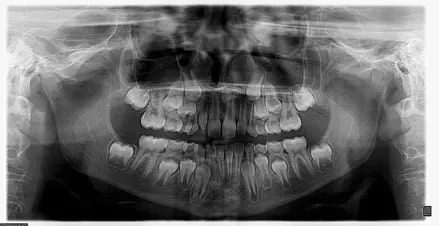

It’s amazing how much more radiographs can tell us about your child’s oral health beyond just cavities. Radiographs can give us important information about the emergence of teeth, diagnose bone diseases, assess an injury’s impact, or plan for orthodontic treatment. This means that we can detect and treat conditions that we cannot see with the naked eye, leading to a smoother and more cost-effective experience for you and your child.

The American Academy of Pediatric Dentistry encourages parents of children with a higher risk of tooth decay to have their children undergo radiographs and examinations every six months. Nonetheless, these types of radiographs are typically only requested from pediatric dentists once a year. Approximately every 3 years, it is a good idea to obtain a complete set of radiographs, either a panoramic and bitewings or periapical and bitewings.